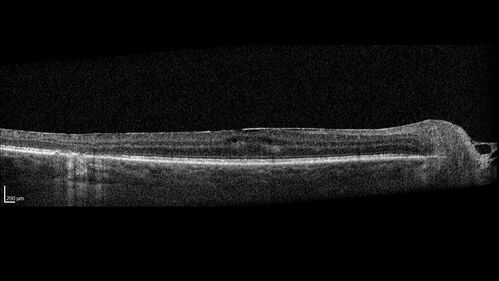

West Nile Virus Multifocal Choroiditis with later CNVM

77 year old female with vision loss in the left eye treated with Anti-VEGF